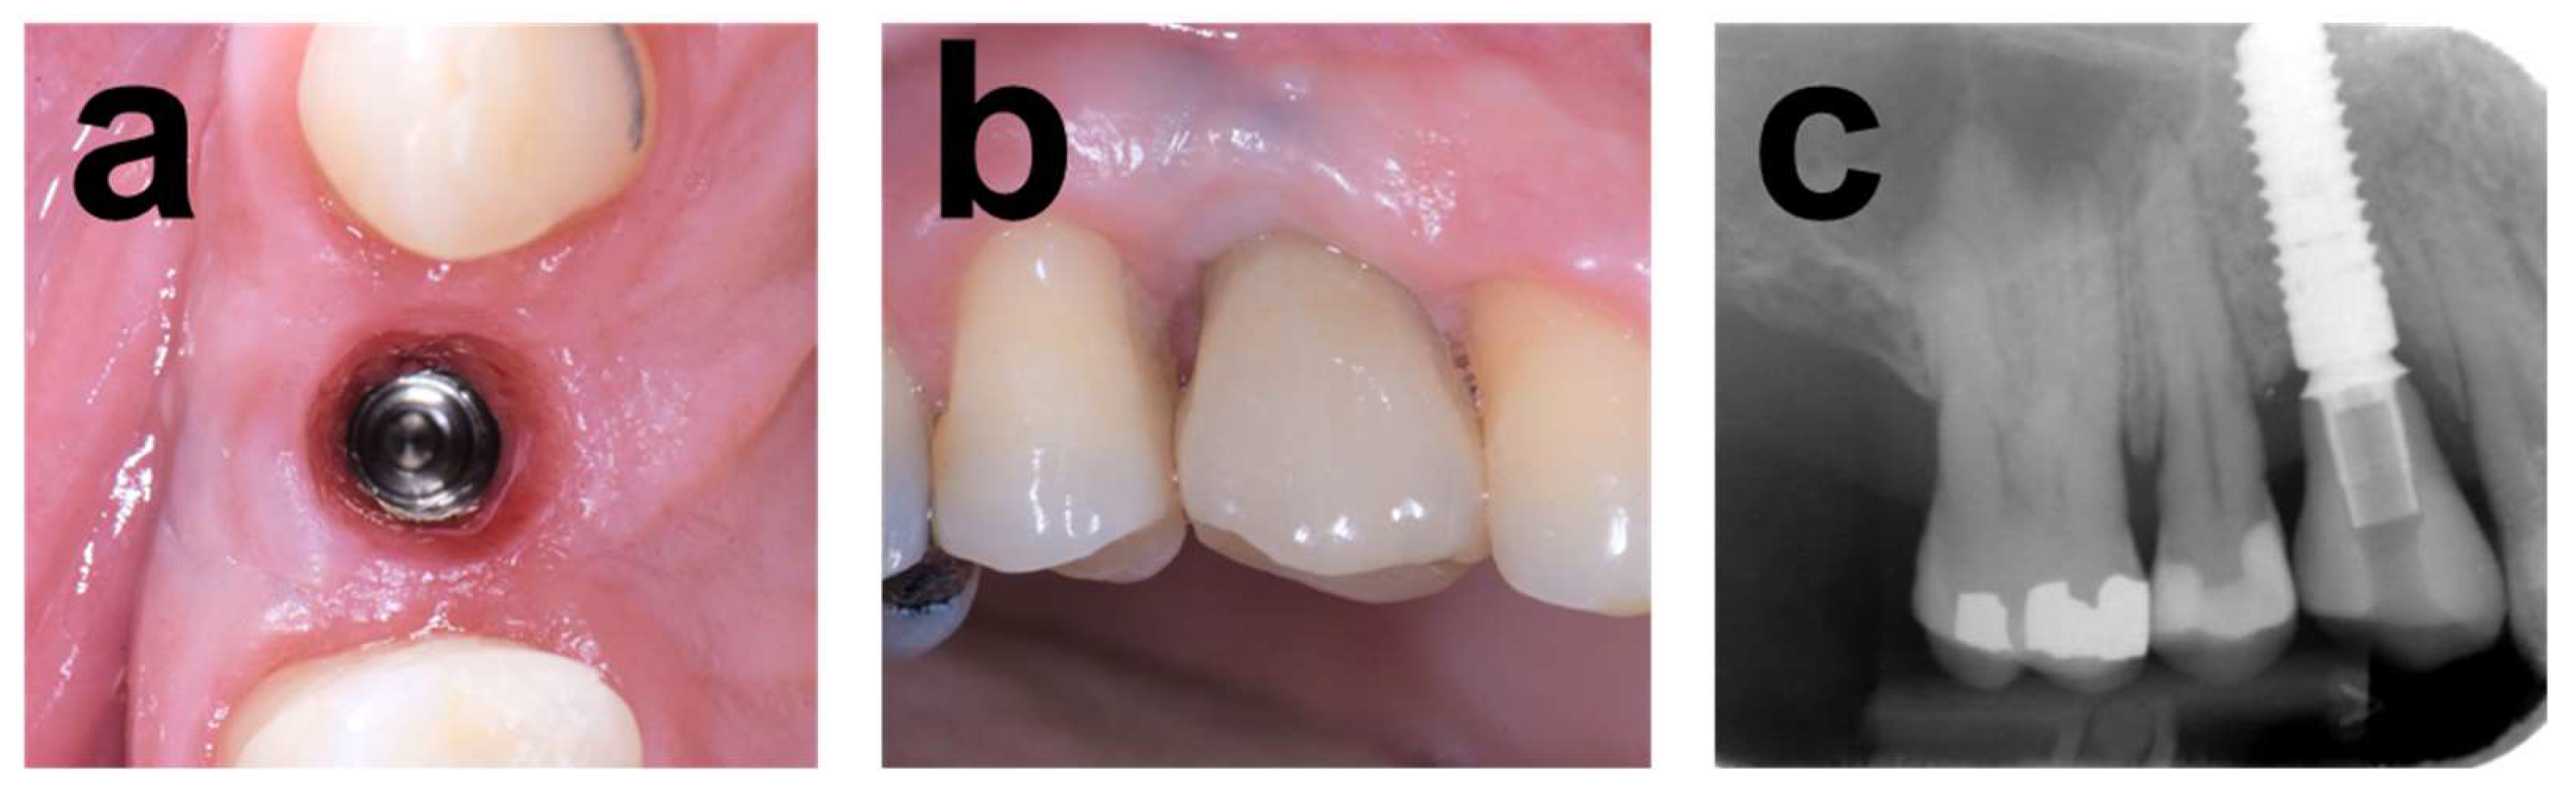

2.7.1. Case 1

2.7.2. Case 2

2.7.3. Case 3

3.1. Clinical Results